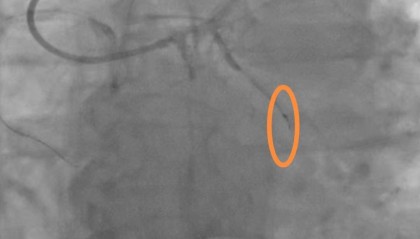

老人手术时导丝断裂掉进血管 医院:外科取出意义不大,补偿8000元

封面新闻记者 石伟 9月28日,河南汝州的高女士反映,她的父亲在河南省胸科医院手术时,手术用的导丝末...